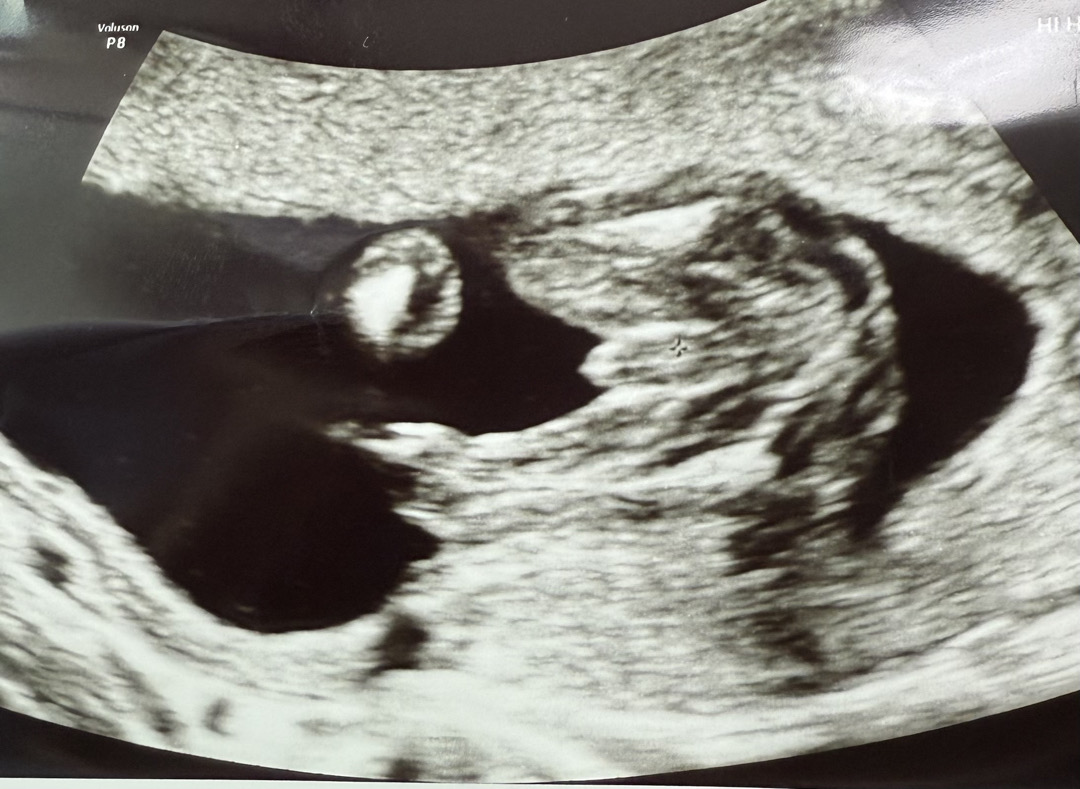

16주 6일 아들 ? 딸?

16주면 다들 어느정도 성별 알수있다해서 기대하고 병원갔는데 이정도면 아들인지 딸인지 확실하지않다고 3주뒤에 오라하시더라구여 15주쯤 서브병원갔을땐 확실히 아들일것같다고 하셨는데..! 사진으로 봤을 때 이정도면 딸로 바뀔 가능성이 있을까요? 아니면 이정도면 아들이 거의 맞을까요?! 아들이여도 딸이여도 좋지만 너무 궁금하네여

헉 모양이 대음순인가 싶기도 하구요..?

헉 정말요!? 저렇게 튀어나와있는데 들어갈수가 있을까여..!

근데 사실 얘기없이 그냥 봤으면.. 아들 같다고 했을 것 같아욬ㅋㅋㅋㅋ 넘 궁금하네요!! 결과 나오면 알려주셔요ㅎㅎㅎ

너무 궁금해서 어제 가봤는데 아들이라고 확정받고왔어요 ㅎㅎㅎ